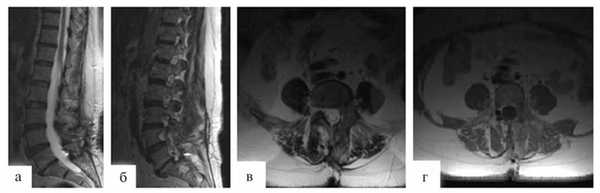

В послеоперационном периоде отмечен регресс болевого синдрома. Пациентка активизирована на 1-е сутки после операции. Спустя 7 дней больная в удовлетворительном состоянии выписана домой. Гистологический диагноз: гемангиобластома. Через 3 мес после проведенной операции выполнено контрольное МРТ-исследование (рис. 3).

Рис. 3. МРТ, выполненные в сагиттальной и аксиальной проекциях в режиме T2 (а, б, в, г). Состояние после радикального удаления гемангиобластомы.